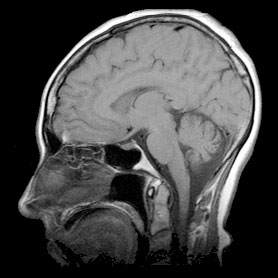

Researchers at the University of Connecticut Health Center (UCHC) are exploring applications of Maple in the interpretation of magnetic resonance imaging (MRI) information for the early detection and characterization of small tumors.

The UCHC team is demonstrating new ways that MRI can be used as a superior way to detect and characterize small (2-4 mm), rapidly growing tumors. This research will enable doctors to use non-invasive MRI to identify and characterize human cancer tumors in their early stages of development and quantitatively follow the course of therapies. To date preliminary results have been done on mice. Clinical trials with human patients are anticipated in the near future.